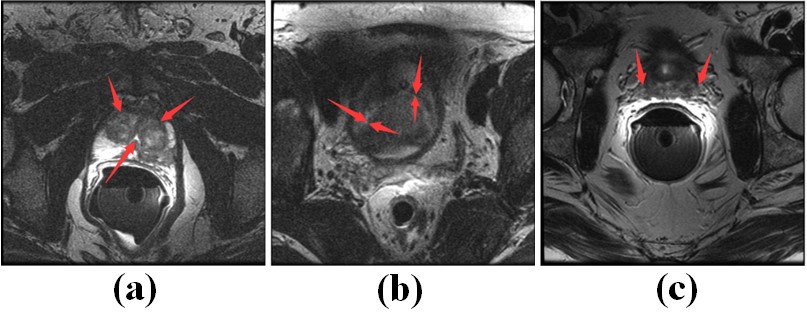

图一:前列腺分割面临的挑战:(a)前列腺区域存在大量的噪声;(b)前列腺边缘模糊;(c)前列腺周边的组织与前列腺的分布特征类似。